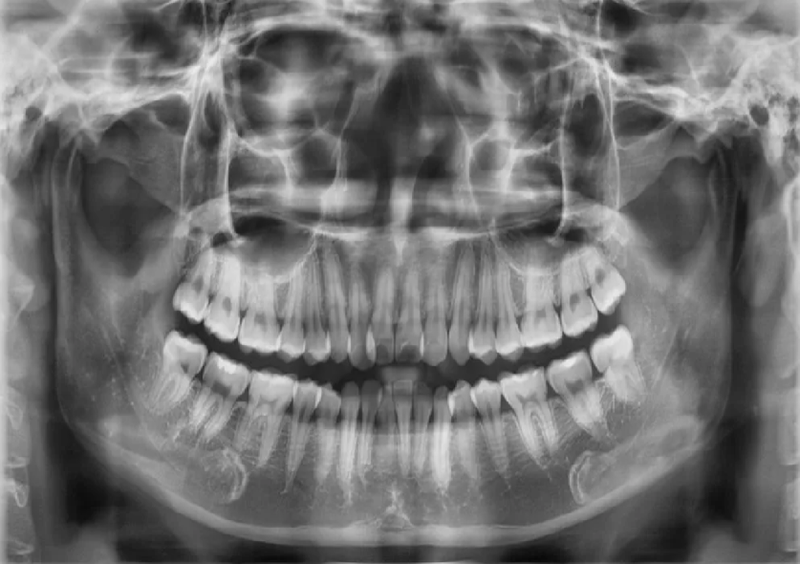

Chụp phim CT cone beam cho kết quả chính xác và đầy đủ nhất 1Chụp phim CT cone beam răng toàn cảnh paranoma

Chụp phim CT Cone Beam hay còn gọi chụp cắt lớp hình nón dùng một loại máy chụp X-quang sử dụng công nghệ đặc biệt để tạo ra các hình ảnh 3D của toàn bộ hàm răng, chỉ qua một lần quét duy nhất. Hình ảnh thu được từ máy chụp CT Cone Beam giúp các nha sĩ có được phác đồ chi tiết, để lên kế hoạch điều trị chính xác cho người bệnh.

Trong quá trình chụp hình răng, tùy theo từng loại máy, người bệnh sẽ ngồi trên ghế hoặc nằm xuống. Máy chụp CT Cone Beam sẽ xoay quanh đầu người bệnh với một góc 360 độ để chụp toàn bộ các góc khó thấy nhất trong hàm răng. Các hình ảnh có độ phân giải cao sẽ kết hợp lại thành một tấm hình 3D duy nhất.